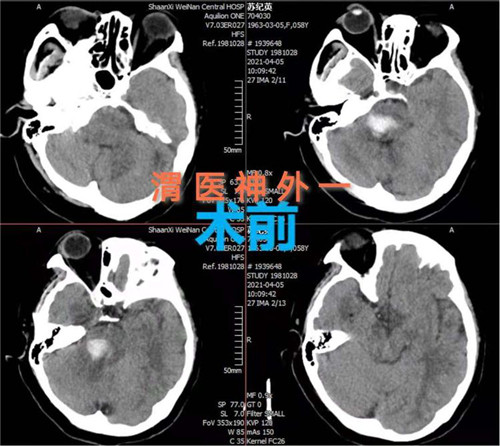

4月5日,市中心医院神经外科一病区通过开颅手术成功救治一例脑干出血患者。该手术的实施和成功填补渭南市该项领域空白,达到省级先进水平。

患者女性,58岁,突然意识不清3小时,行头颅CT检查提示:脑干出血。入院时患者深度昏迷,GCS评分6分。患者脑出血部位特殊,病情危重,手术风险大,并且既往有高血压、糖尿病史,围手术期随时有死亡可能。神经外科一病区赵金安主任带领团队评估手术风险,立刻上报医院,并和家属及时沟通,经反复讨论后最后决定实施开颅脑干血肿清除术:一级入路为右侧乙状窦后入路;二级入路为三叉神经下一面听神经上脑桥侧安全区。

手术计划制定后,即刻安排手术,手术麻醉科确定了由麻醉医师钟永慧、配合护师党海婷和马丹组成的麻醉护理团队。手术历时近4个小时,手术过程患者生命体征平稳,术中总出血量约50毫升,术后患者恢复自主呼吸。术后次日患者生命体征平稳,意识恢复,右侧肢体活动正常,左侧肢体活动正在恢复中。